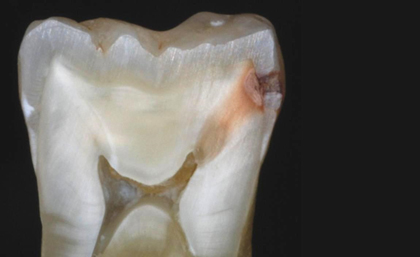

Dişlerde meydana gelen çürük zamanla dişin sert dokularına (mine-dentin) etki ederek yapısını bozmaya başlar. Çürük doku zamanla ilerleyerek dişin içindeki damar ve sinirlerden oluşan dişin canlılığını sağlayan pulpaya yaklaşmaya başlar ve çürük dokunun içinde var olan bakterilerin ürettiği asitler ve atıklarda canlı dokuyu etkilemeye başlar.

Canlı dokunun etkilendiği aşamalarda dişlerde genellikle sıcak gıdalarda ve sıvılarda hassasiyet veya özellikle geceleri kendi kendine meydana gelen ağrılar görülmeye başlar. Tedavi edilmediği zaman bu bakterilerin salgıladığı atıklar ve asitler canlı dokuyu öldürür. Sonuçta canlı dokunun ölümü ile açığa çıkan atıklar ve toksinler(zehirler) kök ucunda olan dar delikten dışarı ilerleyerek çene kemiğinin içerisinde yayılır ve orada apse oluşmasına sebep olurlar.

Apse olarak adlandırdığımız iltihap dokusunu dişe destek sağlayan kemik dokularda harabiyete neden olur ve daha ileri aşamalarda yüzde şişlik meydana gelmesine bile sebep olmaktadır.